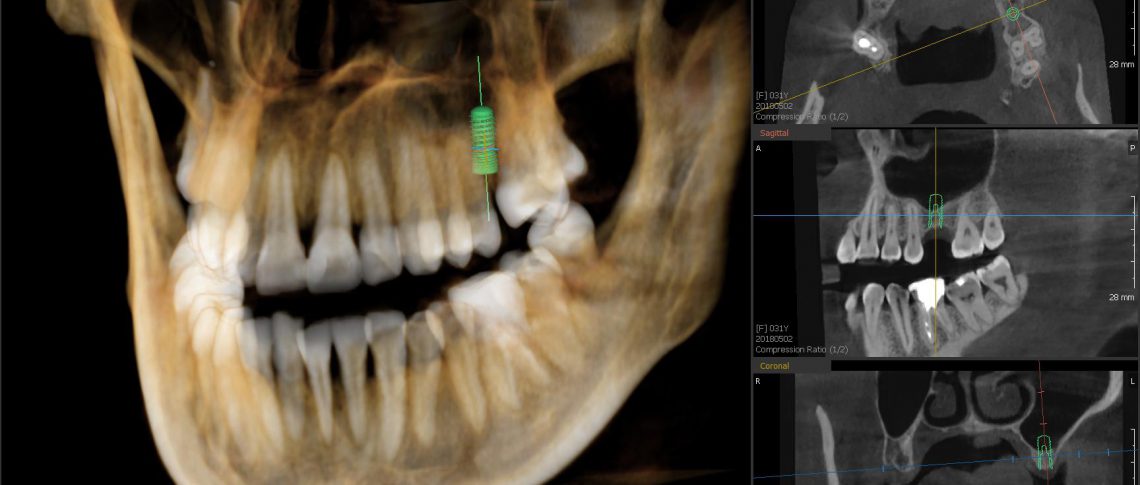

Unikátní OPG a CBCT systém z řady green, vyznačující se vysokou kvalitou snímků a velmi nízkou dávkou záření. Jedním skenováním se vytvoří jak panoramatické, tak 3D zobrazení. Další předností tohoto přístroje je nízká dávka záření, velký objem 3D skenování, redukce kovových artefaktů a unikátní software, umožňující plánování zákroků.